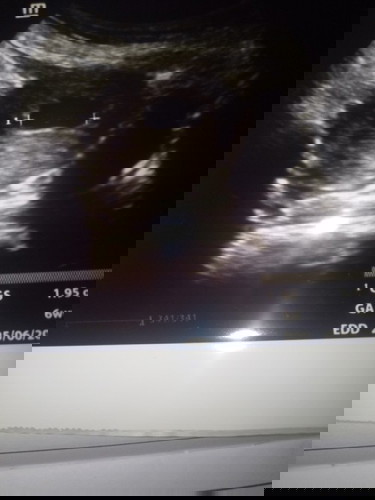

bunda2 dsni ad gak yg sm di mnggu k10 tp janin ny blm kliatn??doktr blng ini BO/blanted ovum,

kayaknya iya BO bun, coba tunggu 2 minggu lg, kalau g ada biasanya dokter saranin kuret